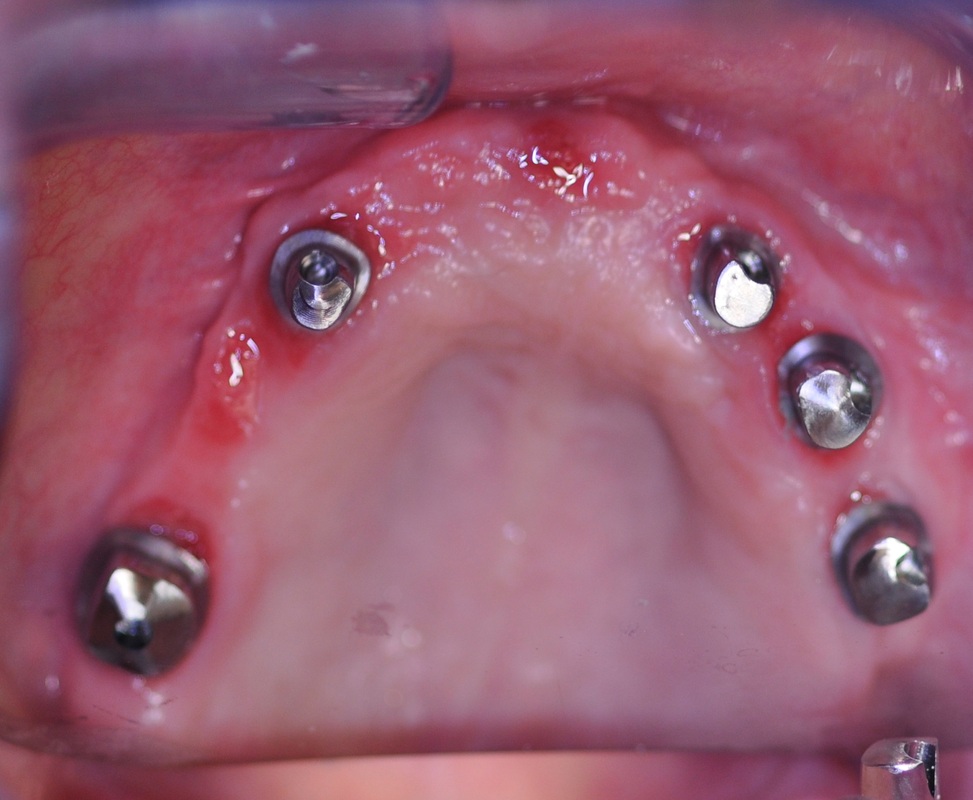

FULL UPPER DENTAL BRIDGE

75-year old teacher was referred to DENTOLOGY by a family member who already had dental implant treatment completed by Dr. Andrews.

She had only few teeth left and the ones remaining didn’t make up a great smile. Full Arch Fixed Dental Implant Bridge option was chosen to rehabilitate her upper arch.

During a single surgery all remaining upper teeth were removed, bone grafts, sinus lifts were done and five dental implants were placed. A few months later this woman was smiling with a million-dollar smile she so long dreamed about.